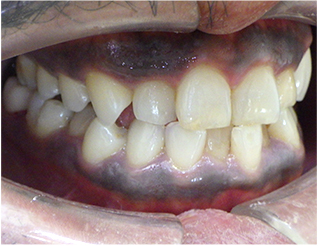

- ブリッジ 症例写真 B-0112FZC3本 女性モニターの方です。

この方は奥歯が虫歯で根だけになってしまっていました。 この歯は抜歯し、ブリッジで治しました。 当院では強度が高く色がきれいなジルコニアブリッジで治しております。 歯型を取らずに、口腔内スキャナーでジルコニアブリッジを作成しますので、精度の高いブリッジを入れることが可能です。 治療回数は3回でした。